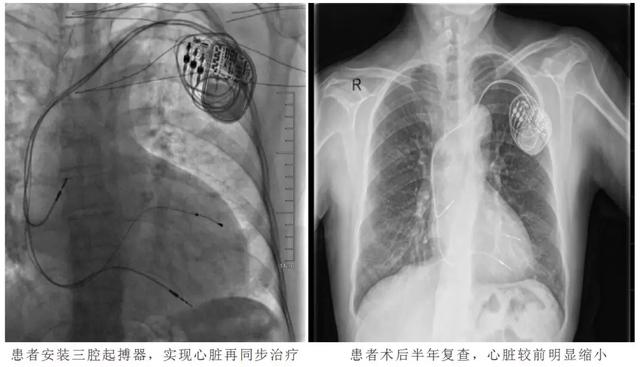

心脏再同步化治疗慢性心功能不全

慢性心力衰竭(心衰)是各类心脏疾病的严重阶段或终末期表现,即使经过充分药物治疗依然预后极差,心脏再同步化治疗(CRT)是心衰患者非药物治疗的重要手段。心脏再同步化治疗作为慢性心衰近二十年来最重要的进展,可有效地改善心功能、降低死亡率、改善预后,大规模的临床研究也证实了这一点。2012年ACCF/AHA/HRS关于CRT的适应症显示:在指南指导的药物治疗(GDMT)基础上,将LVEF≤35%、窦性心律、LBBB且QRS时限≥150 ms、NYHA心功能Ⅱ~Ⅳ级,作为患者接受CRT的Ⅰ类推荐意见。

医院为潍坊地区能独立完成CRT的少数医院之一,近2年,完成CRT手术5例,患者恢复均良好。比如57岁的邢大姨因“发作性胸闷憋气3年,加重半年”入院。患者3年前因胸闷憋气,于外院诊断为“扩张型心肌病”,3年来患者胸闷憋气进行性加重,多次因“心衰”住院治疗,药物治疗效果欠佳。入院心电图示窦性心律,完全性左束支传导阻滞,QRS波时限0.20s。心脏彩超:EF14%,左室舒张末内径71mm。心内二科主任李杰带领医疗团队分析患者病情,具有心脏再同步(CRT)治疗的指征,患者及家属同意后予植入三腔起搏器,实现心脏再同步,以改善心功能,术后患者胸闷憋气明显减轻,心功能由4级恢复到2级,并且心脏明显缩小。